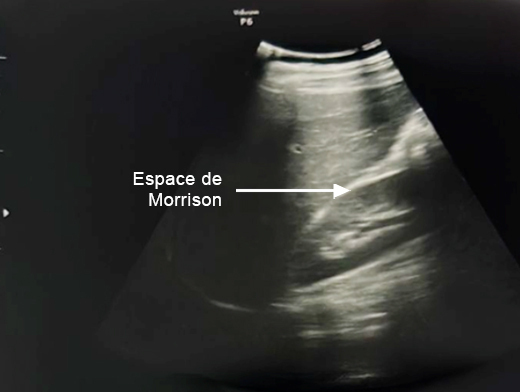

Concernant l’hématome sous-capsulaire du foie : Tableau 3 (Rodolphe Matias de Sousa, La Revue du Praticien) Concernant l’échographie transabdominale à la recherche d’un hémopéritoine :on regarde deux espaces, le cul-de-sac de Douglas entre l’utérus et le rectum, et l’espace de Morrison entre le foie et le rein. Figure 3a (Rodolphe Matias de Sousa, La Revue du Praticien)Figure 3b (Rodolphe Matias de Sousa, La Revue du Praticien)Figure 3c (Rodolphe Matias de Sousa, La Revue du Praticien) Pour rappel, concernant l’échographie en gynécologie : Figure 4a (Rodolphe Matias de Sousa, La Revue du Praticien)Figure 4b (Rodolphe Matias de Sousa, La Revue du Praticien)Figure 4c (Rodolphe Matias de Sousa, La Revue du Praticien)Figure 4d (Rodolphe Matias de Sousa, La Revue du Praticien)Figure 4e (Rodolphe Matias de Sousa, La Revue du Praticien)Figure 4f (Rodolphe Matias de Sousa, La Revue du Praticien)Figure 4g (Rodolphe Matias de Sousa, La Revue du Praticien)Figure 4h (Rodolphe Matias de Sousa, La Revue du Praticien)Figure 4i (Rodolphe Matias de Sousa, La Revue du Praticien)